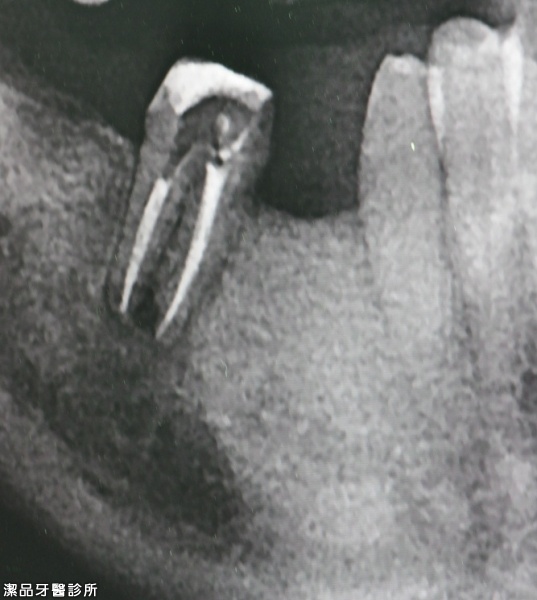

根管重新治療案例-001

案例簡述:

根管重新治療

治療前 嚴重發炎